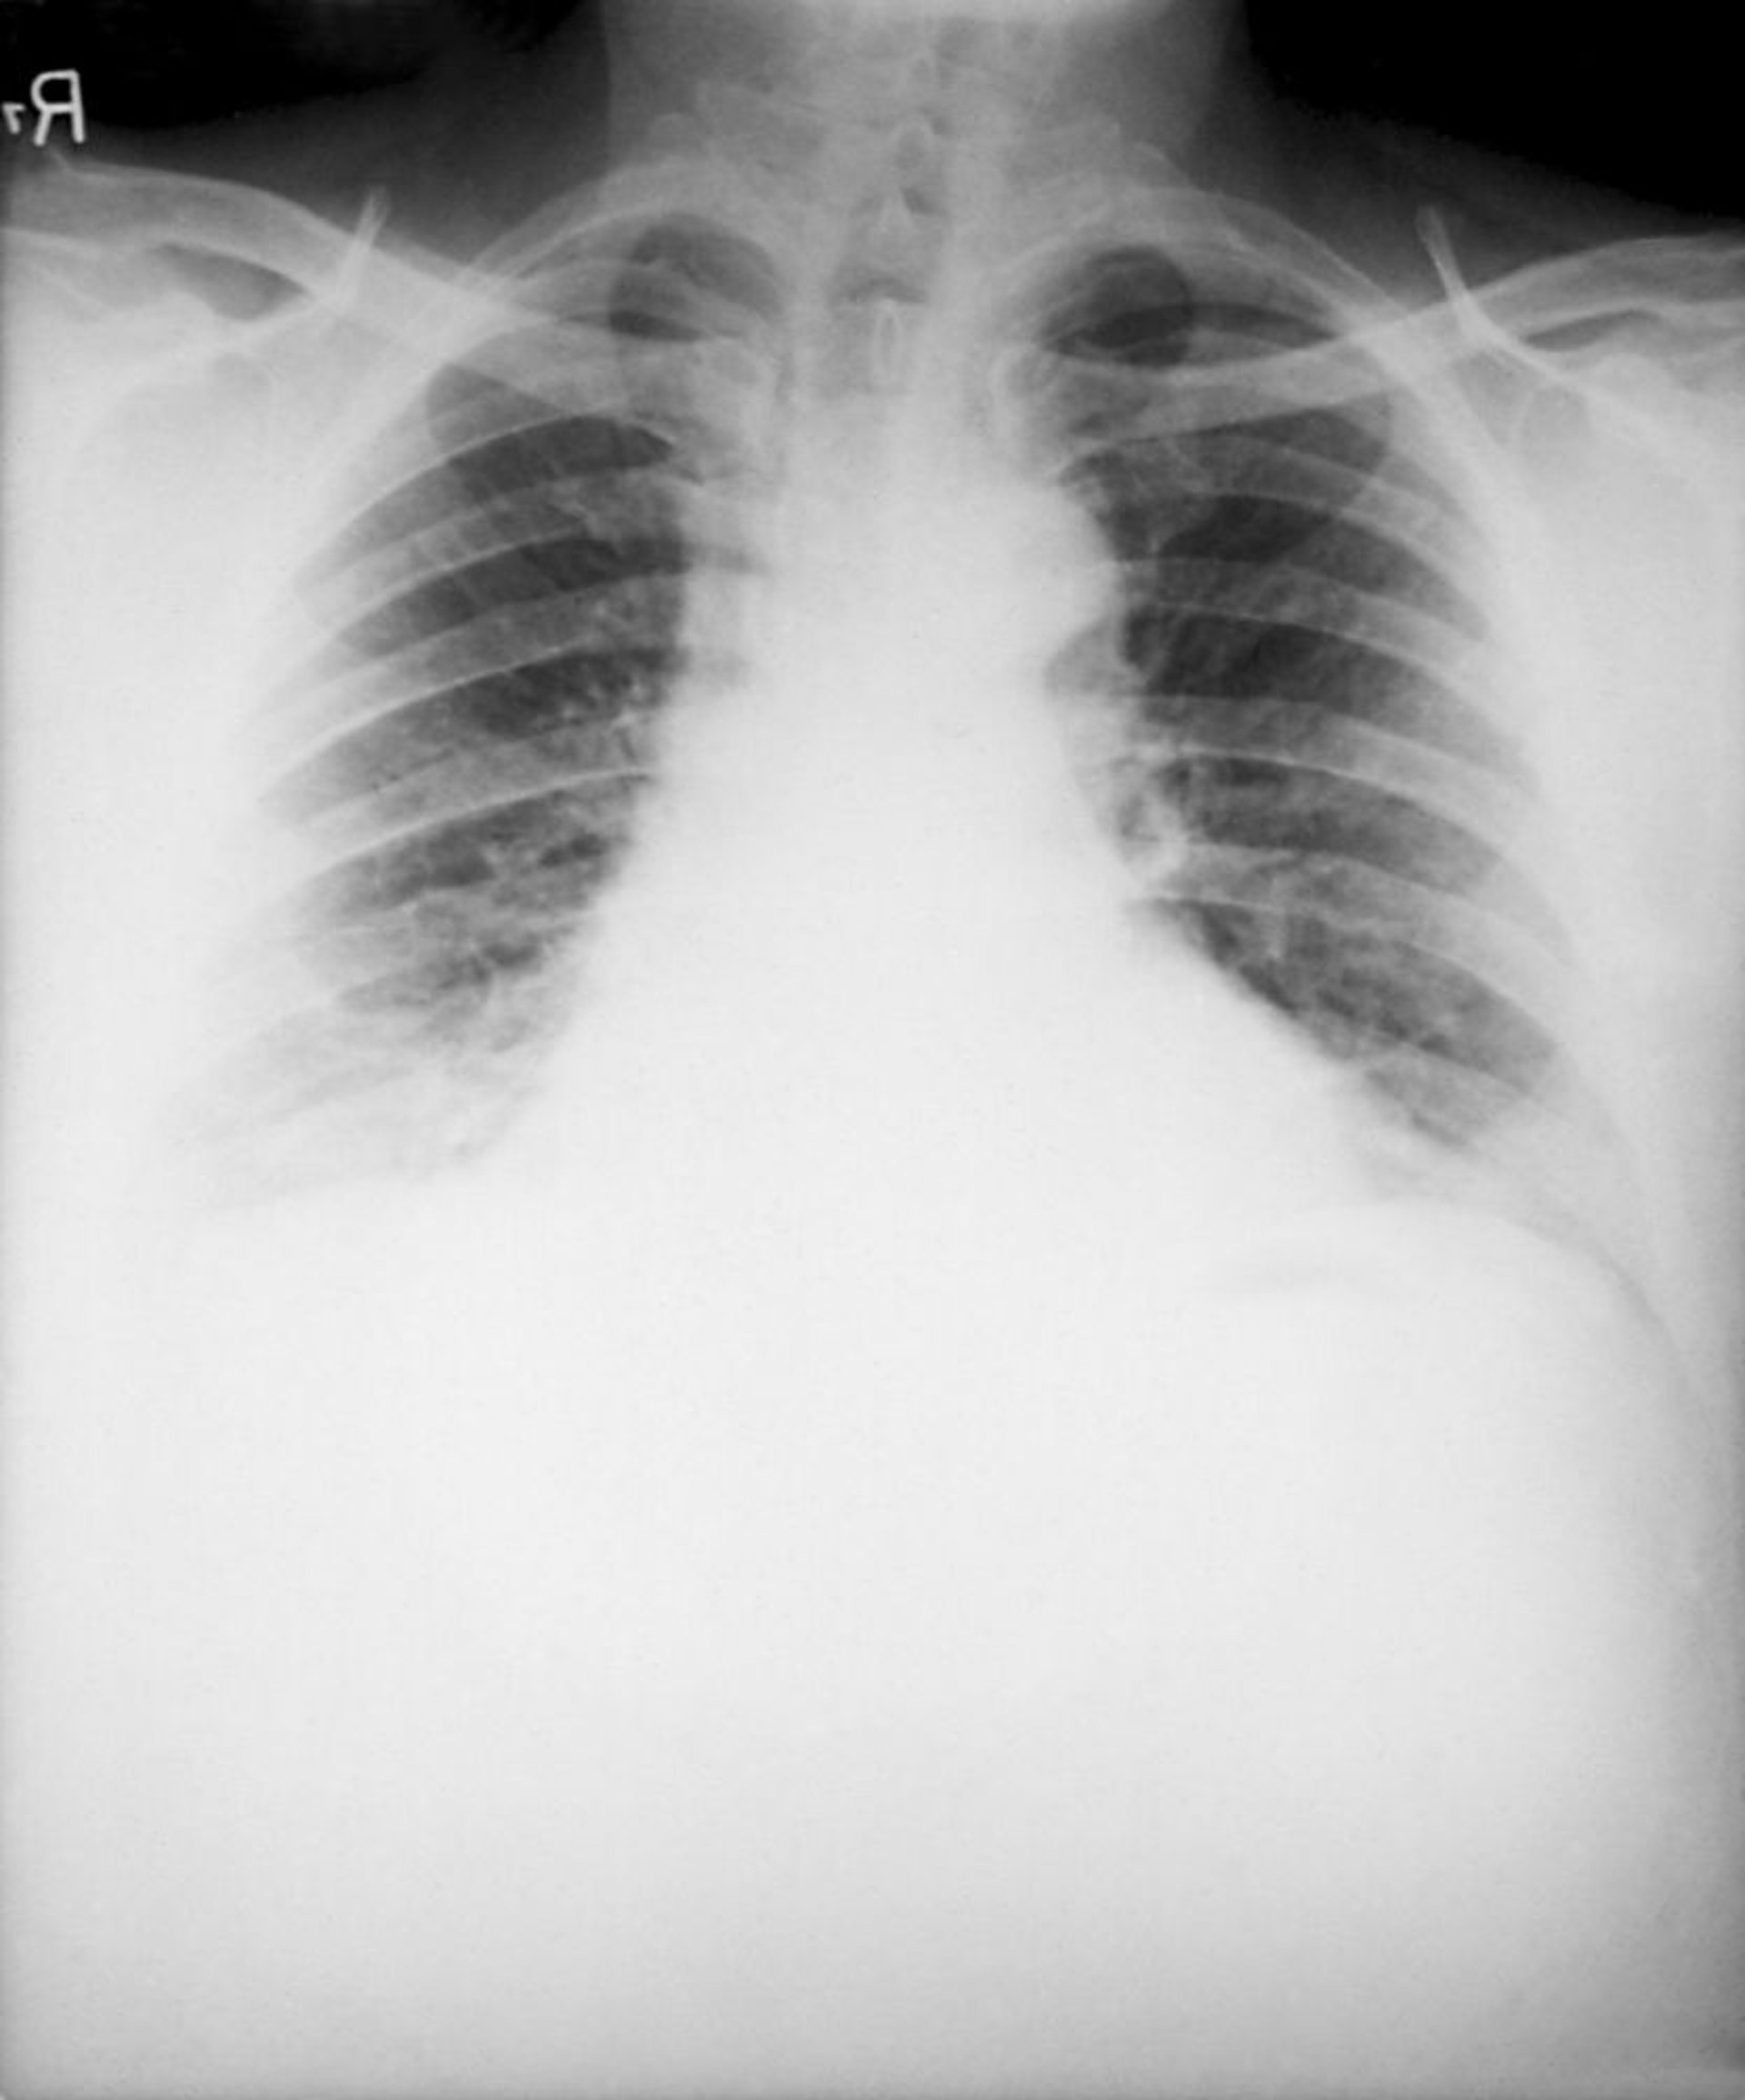

Bệnh than (Do hít phải)

Những dấu hiệu điển hình của bệnh than do hít phải trên X-quang ngực bao gồm một trung thất mở rộng gây ra bởi viêm hạch trung thất hoại tử xuất huyết và tràn dịch màng phổi hai bên. Thâm nhiễm là không phổ biến.

Hình ảnh từ Thư viện Hình ảnh Y tế Công cộng của Trung tâm Kiểm soát và Phòng ngừa Dịch bệnh.